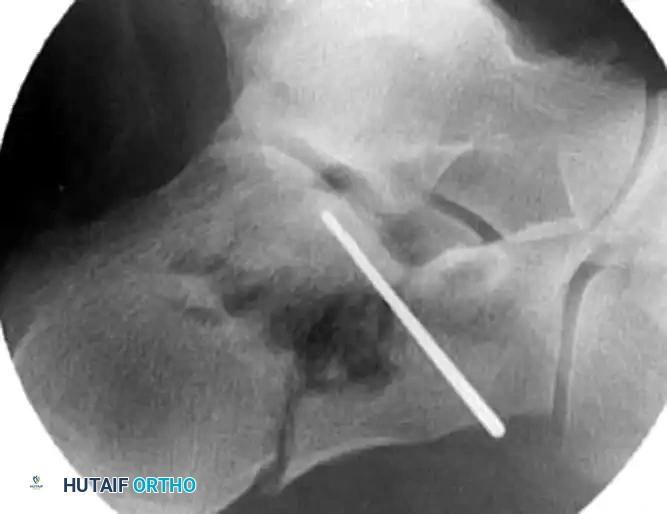

- Make a small stab incision directly over the sinus tarsi, guided by fluoroscopy.

- Introduce a small periosteal elevator or a specialized bone tamp through the incision. Position the instrument beneath the depressed posterior facet fragment.

- Under continuous fluoroscopic guidance (utilizing Broden’s views), gently elevate the articular fragment until it is flush with the "constant" sustentacular fragment.

- Insert multiple smooth Kirschner wires (K-wires) from the lateral aspect of the calcaneus, directing them medially into the dense bone of the sustentaculum tali.

- Verify the position of the K-wires using axial and Broden’s fluoroscopic views to ensure they do not penetrate the subtalar joint or the medial neurovascular bundle.